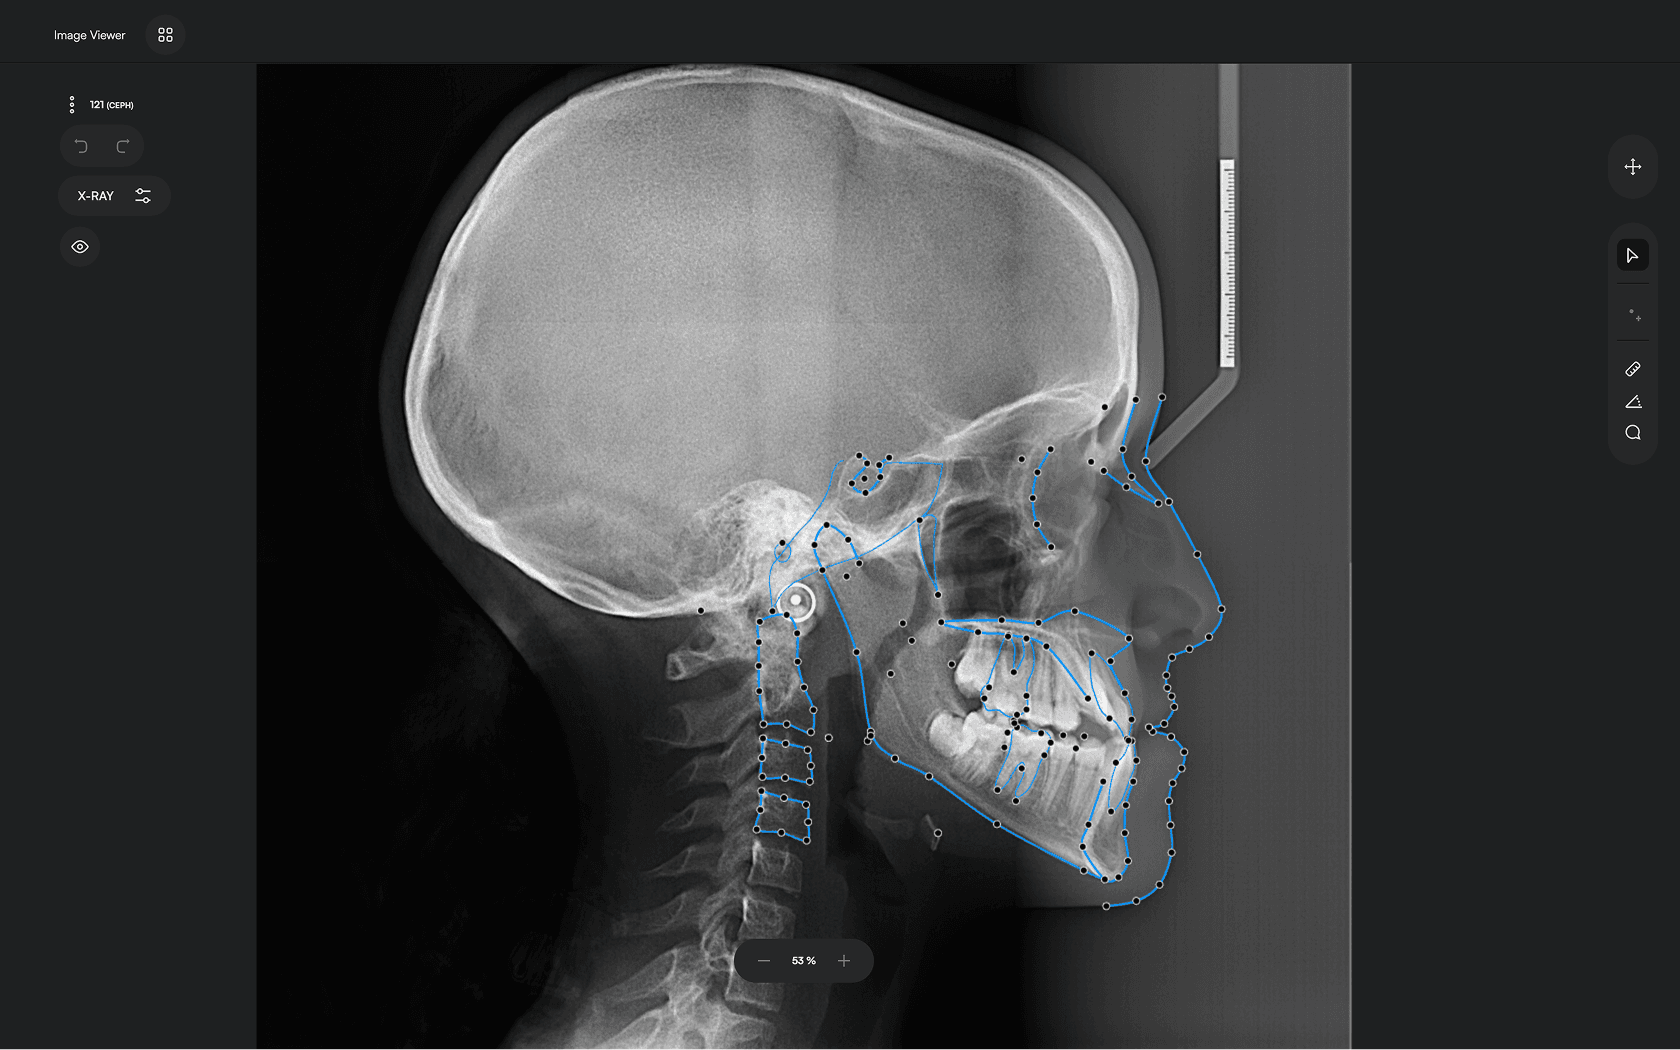

Run AI

Let the software handle tracing and reporting

3

Identify 150+ orthodontic landmarks in under 10 seconds — a task that

traditionally may take more than 30 minutes.